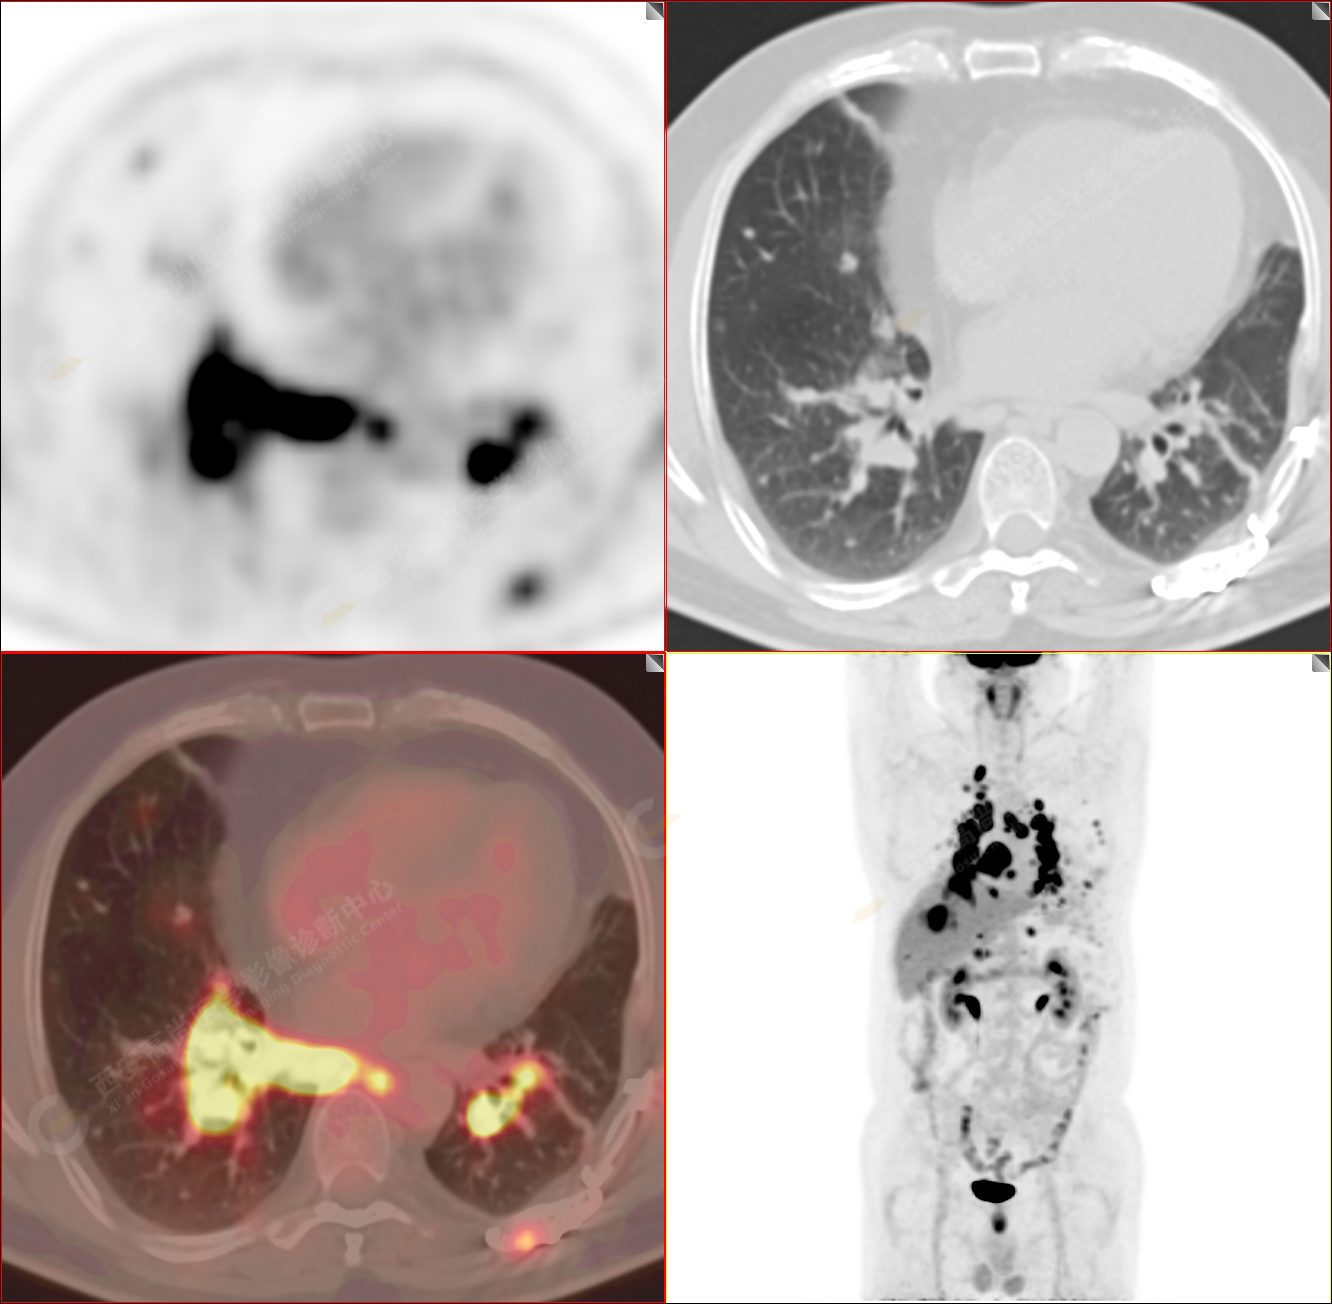

男性,53歲,頭暈半月入院,CT發(fā)現(xiàn)肺內(nèi)腫塊,雙肺多發(fā)大小不等實性及粟粒樣結(jié)節(jié),雙肺門及縱隔多發(fā)腫大淋巴結(jié)。病程中無發(fā)熱、胸悶氣及胸部不適。既往:左側(cè)肋骨外傷史。

PET-MR圖像